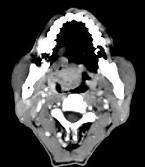

问题 男性,57岁,睡觉打鼾,近来加重,CT扫描如图所示,请选择正确的描述和答案()

选项 A.鼻咽腔偏右侧可见类圆形软组织块影 B.肿块内密度尚均匀,其上方见较多钙化影 C.肿块边缘大部清楚,邻近结构未见明显受侵 D.考虑为鼻咽癌 E.考虑为鼻咽部多形性腺瘤

答案 ABCE